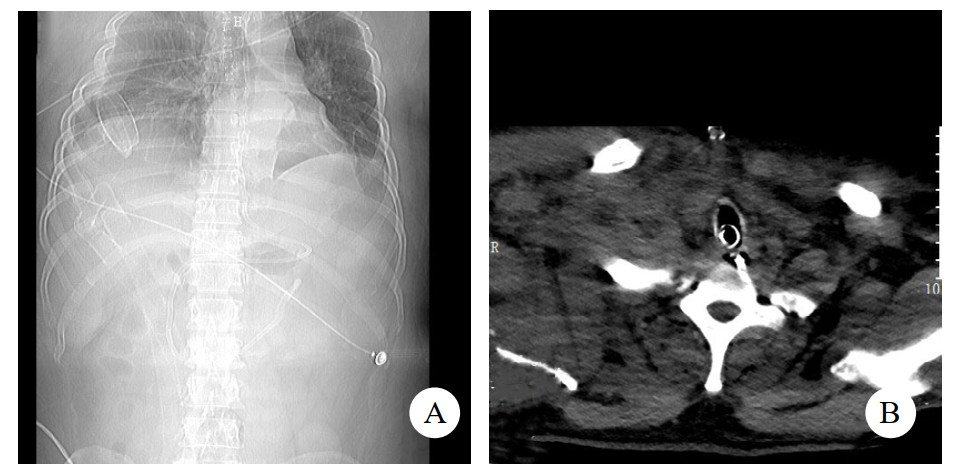

到达我院后由绿色通道急送手术室,心胸外科急行气管修补术,ECMO维持下氧饱和度约93%,经颈部正中切口,术中见主气管上第一、二气管软骨间的气管膜部完全性离断,术中停止呼吸机支持,终止肺通气,完全由ECMO替代,探查上下断端,将断裂膜部与前方气管软骨缝合以完成气管重建。术后转入EICU。ECMO运行中使用肝素抗凝,抗凝策略:肝素125~375 U/h,激活全血凝固时间(activated clotting time of hole blood,ACT)维持在100~140 s,监测HGB稳定于85~101 g/L,5 d后患者病情好转,循环稳定,遂予停用ECMO。7 d后患者意识状态无好转,咳痰能力欠佳,经气管导管吸痰时吸痰导管仅能置入约20 cm,遂予气管镜检查,纤维气管镜探至气管修补处时发现气管软骨下陷导致气道狭窄(图 2),联系耳鼻咽喉科行气管切开术,经颈部正中切口,在下陷气管软骨下置入气管套管,术后予以呼吸机脱机锻炼。10 d后复查胸部CT与入院时相比较,双肺渗出、肺不张、胸腔积液支气管塌陷及胸壁皮下气肿情况均好转(图 3),停机械通气转普通病房康复治疗。

| A:CT检查示双侧气胸吸收好转;B:气管切开套管跨越气管塌陷处 图 3 患者伤后10 d CT影像 |